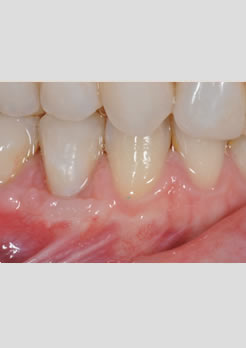

Depois – Dois meses após a cirurgia de enxerto de tecido conjuntivo